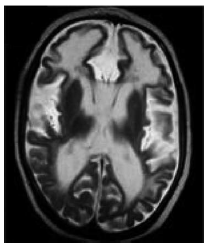

El hipocampo es una estructura crítica para procesar y recordar información espacial y contextual. En base a esta premisa, se pretende evaluar el papel de esta estructura del lóbulo temporal medial en una tarea de aprendizaje espacial: el laberinto acuático de Morris. El laberinto de agua fue diseñado en 1984 por Richard G. Morris para estudiar y evaluar el aprendizaje y la memoria espacial en ratas de laboratorio. El laberinto acuático es una piscina circular llena de agua a una temperatura que oscila entre los 18 y los 27° C, según se utilicen ratas o ratones, en la que se sumerge una plataforma que debe ser localizada por el animal. El agua se vuelve opaca con leche o alguna sustancia no tóxica como el látex para que el animal no vea la plataforma, aunque se ha demostrado que esto no es necesario, ya que el animal nada con la cabeza por encima del agua, lo que le impide ver la plataforma.

En la versión tradicional del laberinto, los sujetos experimentales nadan desde diferentes puntos de salida, situados en el perímetro de la piscina, hasta encontrar la plataforma escondida bajo el agua. Para localizar la plataforma, el sujeto depende de unos puntos de referencia, lo cual implica un amplio rango de posibilidades tales como pequeños objetos localizados inmediatamente alrededor de la circunferencia de la piscina.

Imagínese que se quiere llevar a cabo un experimento para evaluar si las lesiones bilaterales del hipocampo deterioran el aprendizaje espacial en ratas utilizando esta tarea. Para ello, se diseña un procedimiento con dos condiciones experimentales: (A) intervención quirúrgica sin lesión hipocampal, (B) lesión bilateral del hipocampo. En este tipo de diseño, no podemos utilizar una estrategia de comparación intrasujeto, ya que la manipulación de la VI hace que la condición experimental sea irreversible. Si se utiliza el contrabalanceo como técnica de aleatorización, únicamente podría llevarse a cabo el orden de presentación de los niveles de la VI AB, pero no el orden BA (ya que la lesión del hipocampo hace la situación irreversible). Para llevar a cabo este experimento, necesitaríamos utilizar una estrategia de comparación intersujeto y comparar grupos independientes. Si la muestra es suficientemente grande y se utiliza un procedimiento probadamente aleatorio para asignar los sujetos a las condiciones experimentales, podemos asumir que las variables extrañas se equilibrarán formando grupos equivalentes.

Figura 21. Ejemplo de contrabalanceo: estudio del hipocampo.